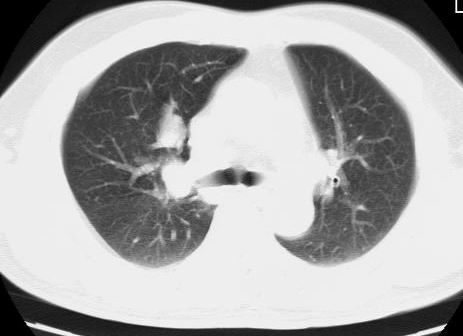

标题: CT15869:男性,71岁,因咳嗽而就诊,请讨论右上肺病变性质 [打印本页]

标题: CT15869:男性,71岁,因咳嗽而就诊,请讨论右上肺病变性质

患者,男性,71岁,因咳嗽而就诊,

典型的右肺中心性肺癌并纵隔淋巴结转移

右肺中心性肺癌并纵隔淋巴结转移可能性大!

考虑右肺中心性肺癌并右肺门及纵隔淋巴结转移。

1,右肺中心型ca,气管隆突旁淋巴结转移。